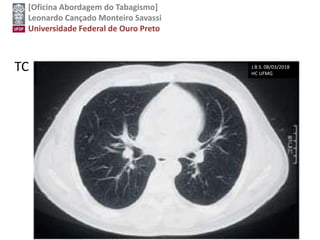

TC J.B.S. 08/03/2018

HC UFMG

Screening Tests

Low-dose computed tomography has shown high

sensitivity and acceptable specificity for the

detection of lung cancer in high-risk persons.

Chest radiography and sputum cytologic

evaluation have not shown adequate sensitivity or

specificity as screening tests. Therefore, LDCT is

currently the only recommended screening test for

lung cancer.

USPSTF, 2014